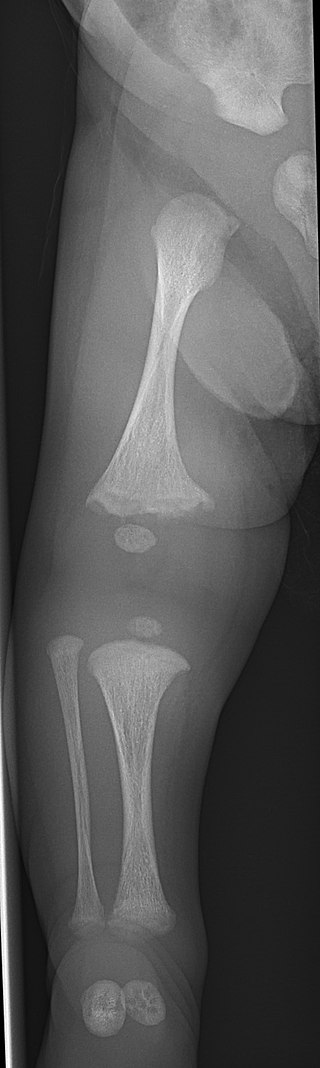

Osteopetrosis

Osteopetrosis is due to a hereditary deficiency in bone resorption.

Osteopetrosis causes abnormally thick, heavy bone that is brittle and easily fractures.

Multiple genetic variants exist, and carbonic anhydrase mutation leads to loss of the acidic microenvironment required for bone resorption.

Clinical features of osteopetrosis include:

- Bone fractures

- Anemia

- Thrombocytopenia

- Leukopenia

- Extramedullary hematopoiesis due to bony replacement of the marrow space

Impingement on cranial nerves due to bony overgrowth may cause characteristic neurologic symptoms based on the cranial nerves that are affected.

Osteopetrosis most often causes vision and hearing loss.

A carbonic anhydrase mutation causes renal tubular acidosis, while a lack of carbonic anhydrase causes poor HCO3 tubular reabsorption, which results in metabolic acidosis.

Treatment of osteopetrosis is bone marrow transplant since osteoclasts are derived from monocytes.